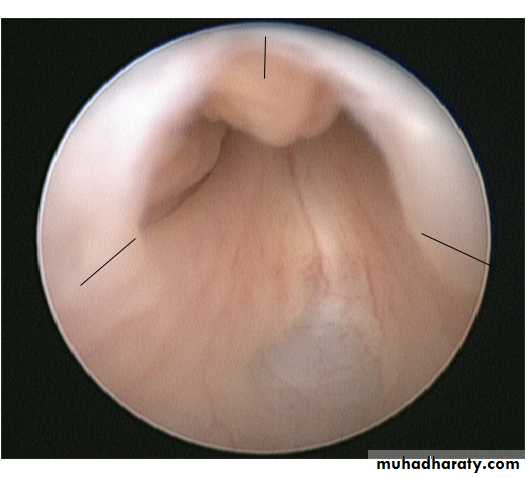

A posterior urethral valve is an obstructing membrane in the posterior male urethra as a result of abnormal embryological development and it is the most common cause of bladder outlet obstruction in male neonate.The embryological abnormality giving rise to posterior urethral valves is thought to represent either an anomalous insertion of the mesonephric duct into the uro-genital sinus, preventing normal migration of these ducts and their anterior fusion or a consequence of an abnormality of the cloacal membrane.

Ultrasound scan of kidneys and bladder.VCUG shows distended and elongated posterior urethra; partially filled anterior urethra; bladder neck hypertrophy; lucencies representing valve leaflets; thick-walled bladder (±diverticuli); incomplete bladder emptying; reflux (50%).

Commence prophylactic antibiotics immediately, check serum electrolytes, and drain the bladder with a pediatric feeding tube. If there is improvement, cystoscopy and transurethral ablation of valve If upper tracts remain dilated with raised creatinine after bladder drainage, a temporary cutaneous vesicostomy is indicated. An alternative is ureterostomy drainage. Valve ablation is performed at a later stage.

Treatment: endoscopic valve ablation